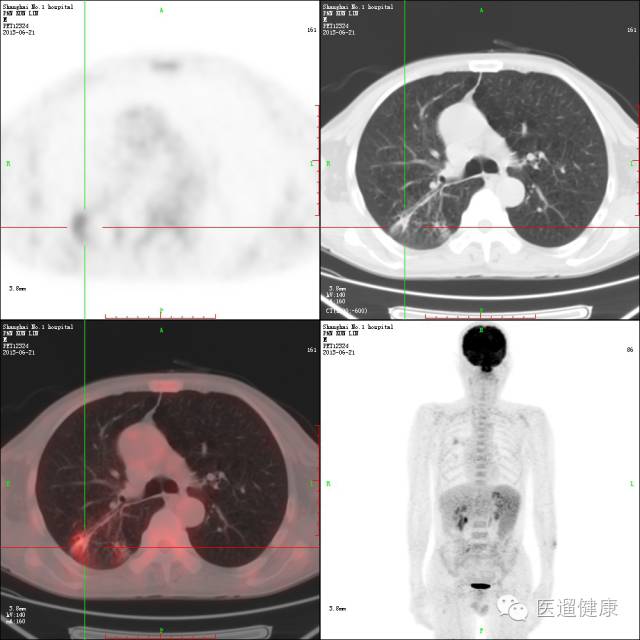

案例三、

PET/CT协助淋巴瘤首次分期病例

病患:女,64岁,左眼疼痛、视力下降一月余。

外院MRI提示左蝶筛窦炎。

左筛窦内窥镜手术,病理:左筛窦NHL(非霍奇金淋巴瘤)(DLBCL)。

入院时初步分期:IA期。

PET/CT显像目的:协助临床准确分期。

↑

分期上调为IIIA期

→

左海绵窦增宽,左视神经孔受压,前床突骨质硬化并边缘骨质侵蚀,SUV最大值约13.2

该病例通过

PET/CT后分期上调为IIIA期